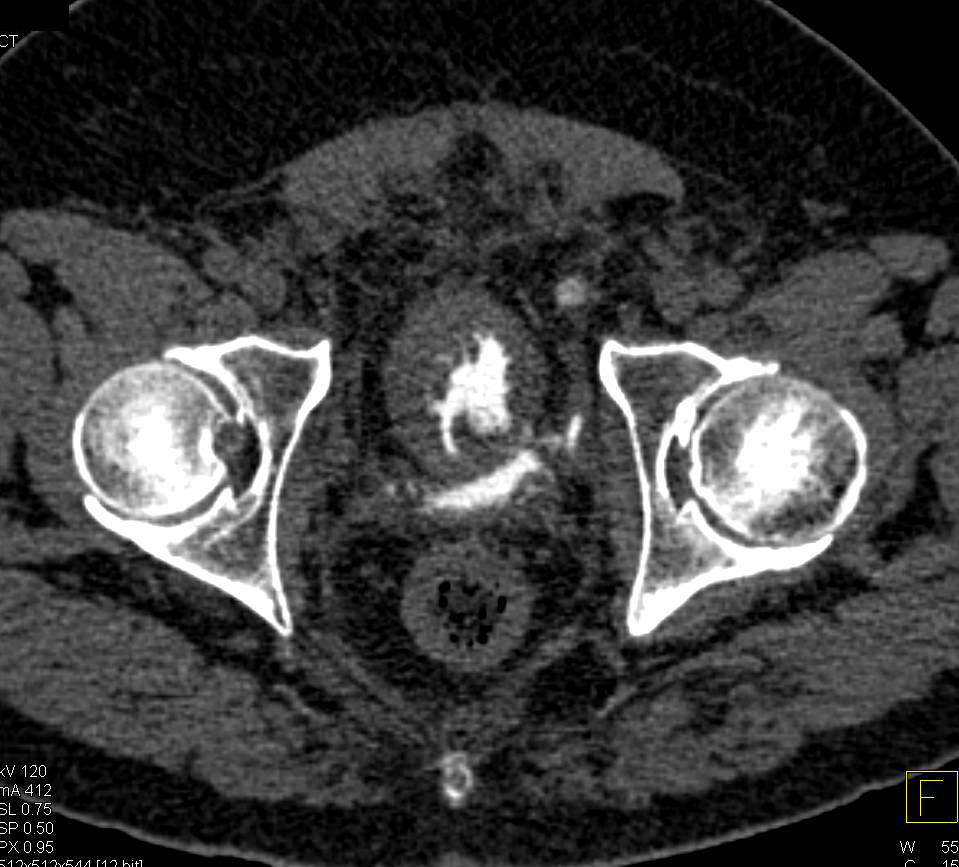

CT Cystogram Shows Extraperitoneal Bladder Rupture Following a Laparoscopic Prostatectomy